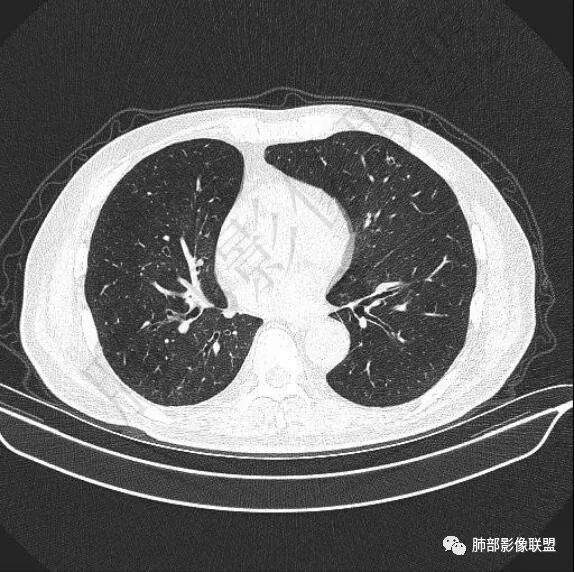

二..发现左肺上叶舌段实性密度小结节影,不规则略呈半环形,边界清楚,未见分叶、毛刺及磨玻璃晕。未见卫星病灶。

9个月后病灶明显增大,边缘较平直,部分膨隆,锁扣样外观,仍旧缺乏典型深分叶及张力,未见胸膜凹陷。

再1个多月后病灶继续增大,较明显不均匀强化,肺门一侧见低密度区。病灶边缘相对不清,可见毛刺。

三.病程脉络相当清楚,即病灶进行性增大,易想到新生物或转移瘤,但经验上分析增长速度显然太快,尤其是对于原发肺腺癌或者肺鳞癌而言,单发转移瘤也较少这样的进展速度。